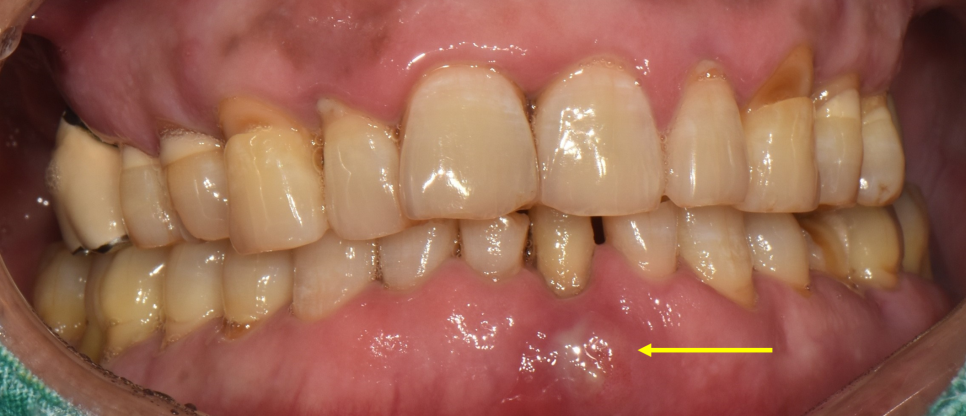

23.09.12(발치+임플란트식립) – 57y 김OO님

수개월 후에 아래 앞니가 부러지셨다며

내원하셨을때 촬영한 입안 사진입니다.

노랑색화살표 치아인데요,

딱딱한 것을 씹다가 부러졌다고 하셨는데

오래전에 신경치료 및 크라운 치료를 한 부분이

약해져서 부러진 것으로 보입니다.